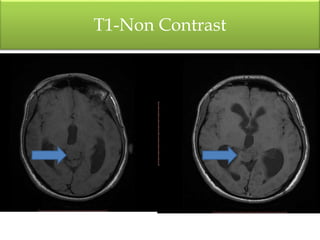

T1-Non Contrast

• Soft tissue mass lesion measureing2.9 X 2.7 X 2.7 cm

• Hypointense T1,hyperintense T2 / FLAIR signal &

homogenous post-contrast enhancement

• Lesion is compressing the superior portion of the cerebral

aqueduct with moderate supratentorial hydrocephalus